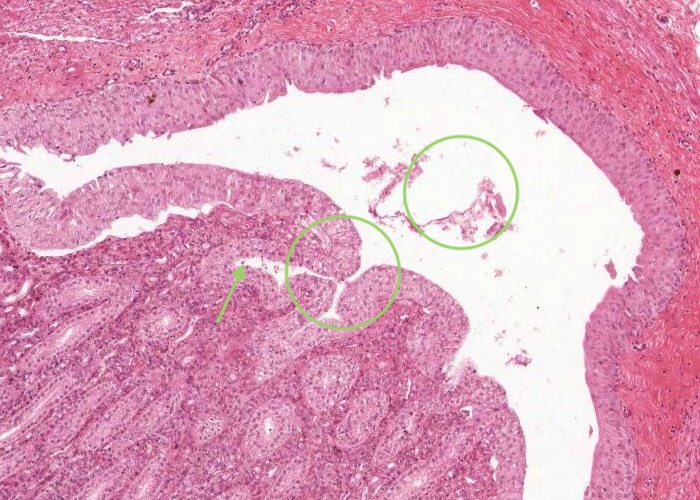

At low magnification, observe the three layers of the ureter: mucosa, muscularis and adventitia. This organization is maintained throughout the urinary passages. The mucosa of the ureter is thrown into characteristic longitudinal folds. It is made of transitional epithelium underlain by a layer of fairly cellular connective tissue (lamina propria). Quite a few lymphocytes are found in this lamina propria. The muscularis layer consists of two somewhat diffuse sheets of smooth muscle: the inner is longitudinal, and the outer is circular. Towards the bladder end it picks up a third oblique layer. This muscle produces peristaltic waves that push the urine to the bladder even when you are lying down. The adventitia is made of connective tissue and contains the nerves and blood vessels that supply the organ. One thing to note is that the ureter runs through loose connective tissue from the kidney to the bladder.

The ureter and also the other passages within the kidney through which urine flows i.e. the calyces and renal pelvis, are lined by transitional epithelium (often referred to as urothelium). The details of the layers of cells within this type of epithelium is best described in the later item "lumenal epithelium" of the bladder but generally it is 2-3 cell layers thick in the minor calyces but much thicker as you see here in the ureter and then the bladder.

Connective tissue and smooth muscle make up the remainder of the wall of the ureter. The smooth muscle is in longitudinal and circular layers so when you examine the section see if you can pick out these longitudinal and circular layers of muscle.